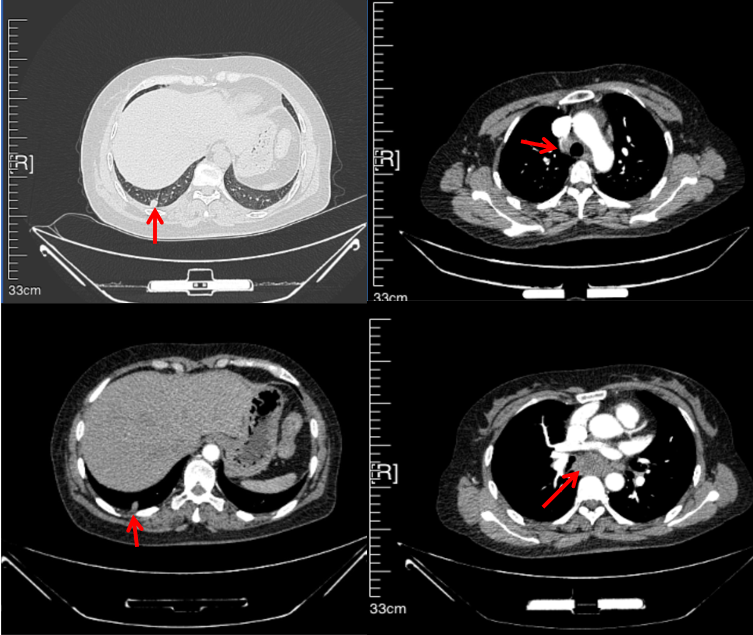

2016年1月复查CT提示支气管截断可见新发小结节,一线治疗采用培美曲塞+DDP方案化疗4周期(培美曲塞3.36,DDP 480mg)。化疗后复查胸部CT:右肺见不规则结节样影,最大层面大小约19mm*8mm,较前比较明显增大,疗效评估PD。2017.3-2017.4予单药多西他赛化疗3周期,疗效评估SD。2018年5月末复查CT提示结节较前增大,评效为PD,2018年6-10月予多西他赛+CBP化疗4周期,疗效评估SD。2022年5月患者出现活动后气短,复查胸部CT示右肺膨胀不良;右侧胸腔积液增多。胸腔积液包埋病理示符合肺腺癌细胞。行NGS基因检测:EML4:exon13-ALK:exon20融合。PD-L1(克隆号22C3)TPS<1%。

2018.07

2022.05

2022.08

2023.05

2024.12